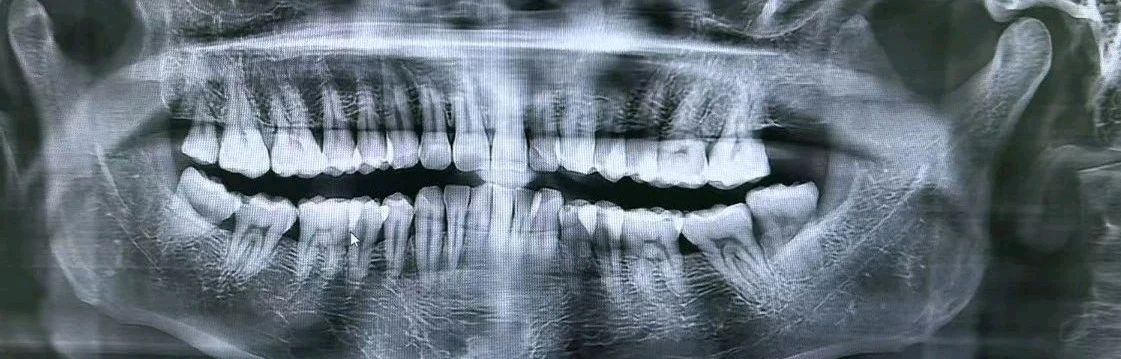

首先拍了个牙齿的片子,推测应该是X射线之类的,头上的金属发卡什么的都要摘掉,然后前排牙齿咬着一个塑料的小原片,射线围着头转了一圈,片子就拍好了,护士还要我用手机拍下来,是不是以后再拔牙就不用拍了的意思,不过真不喜欢拍这种,麻烦。

牙医看了片子说可以拔牙,于是就躺在那个床上等着。说实话,其实心里忐忑的要死,毕竟距离上一次这样拔牙已经过去了17年,早就忘了拔牙的痛,偏偏自己又是对疼痛很敏感的人,于是有点过于紧张。一边询问整个过程要多久,一边做好心理建设,好在听到医生说整个过程也就10分钟,顿时安心了不少。只是不知道为什么要给我打两次麻药,等到嘴唇还开始麻的时候,开始整活了。只见他拿着一个像螺丝刀一样的工具开始在我的牙齿上生拉硬拽,还好没啥感觉,正当我疑惑这牙好不好拔的时候,他突然来了句,“拔完了”,不禁惊呼“啊?这么快!”可是他没有停下手中的动作,好像还在那个牙的位置一直捣鼓,我问他问了两遍,他说是在缝针,好像是用线把伤口缝一下促进愈合,我还想问一下,结果医生反而不耐烦了,“跟你说了两遍,是缝针,一周后过来拆线”,好家伙,白长那么帅了,差评,医患关系就是这么恶化的!